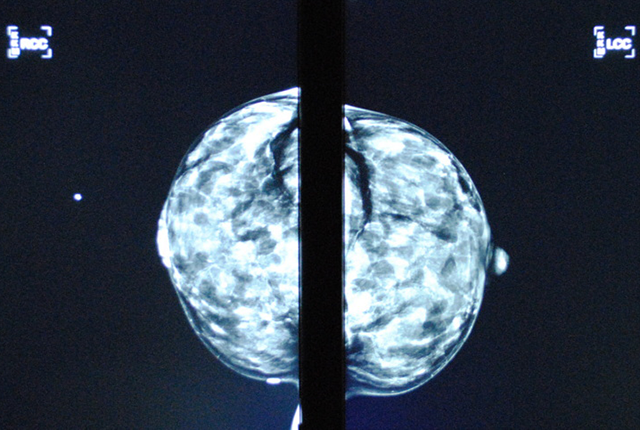

Q&A: If you’re just finding out you have dense breasts

An FDA mandate means that millions more U.S. women will get their first such notice this year. A mammography expert offers context.Media Contact: Brian Donohue - 206-543-7856, bdonohue@uw.edu

Photo credit: The breast scan image, published by Leah Small, was republished under Creative Commons License 2.0.